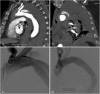

Objectives: To demonstrate the various presentations of acute aortic pathology and to present diagnostic and therapeutic approaches.

Methods: Diagnostic imaging is the key to the reliable diagnosis of acute aortic pathology with multi-slice computed tomography angiography (CTA) as the fastest and most robust modality. Endovascular aortic repair (EVAR) with stent grafts and open surgical repair are therapeutic approaches for aortic pathology.

Results: CTA is reliable in diagnosing and grading aortic trauma, measuring aortic diameter in aortic aneurysms and detecting vascular wall pathology in acute aortic syndrome and aortic inflammation. CTA enables planning the optimal therapeutic approach. Stent graft implantation and/or an open surgical approach can address vascular wall pathology and exclude aortic aneurysms.

Conclusion: Aortic emergencies have to be detected quickly. CTA is the imaging method of choice and helps to decide whether elective, urgent or emergent treatment is necessary with EVAR and open surgical repair as the main treatment approaches.

Teaching points: • To present aortic pathology caused by trauma • To present acute aortic syndrome (aortic dissection, intramural haematoma and penetrating ulcers) • To present symptomatic and ruptured aortic aneurysm • To present infection (mycotic aneurysms/aorto-duodenal fistulae) or iatrogenic injury of the aorta • To understand different presentations for treatment planning (EVAR and open surgery).